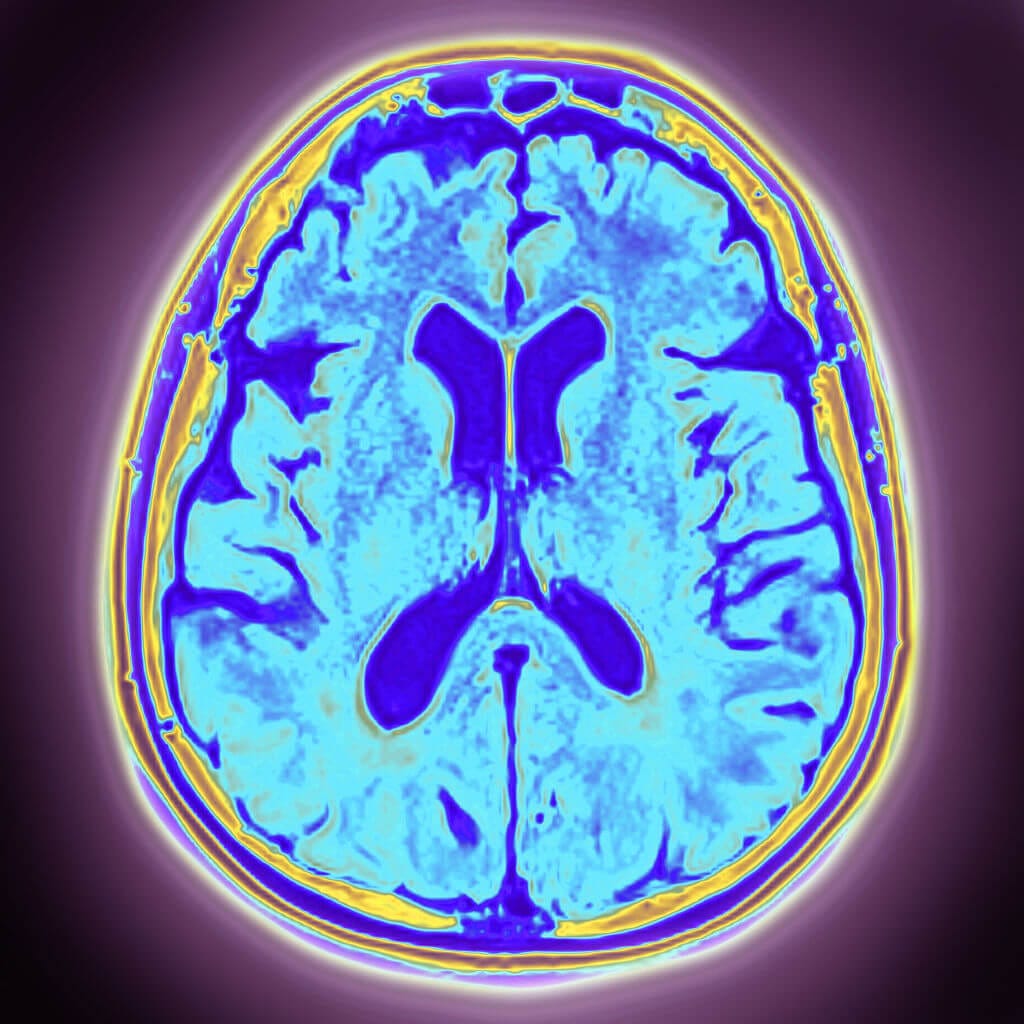

Neuroimaging is used to support a suspected diagnosis of DLB. Positron emission tomography (PET) may reveal glucose hypometabolism in the medial temporal and occipital lobes2,22,23; dopamine transporter scans can identify reduced uptake in the basal ganglia18,24,25; and magnetic resonance imaging can help rule out other disorders.7 Imaging can be used to assess peripheral tissues as well. Meta-iodobenzylguanidine cardiac scans may demonstrate decreased uptake, reflecting loss of autonomic neurons.2,14